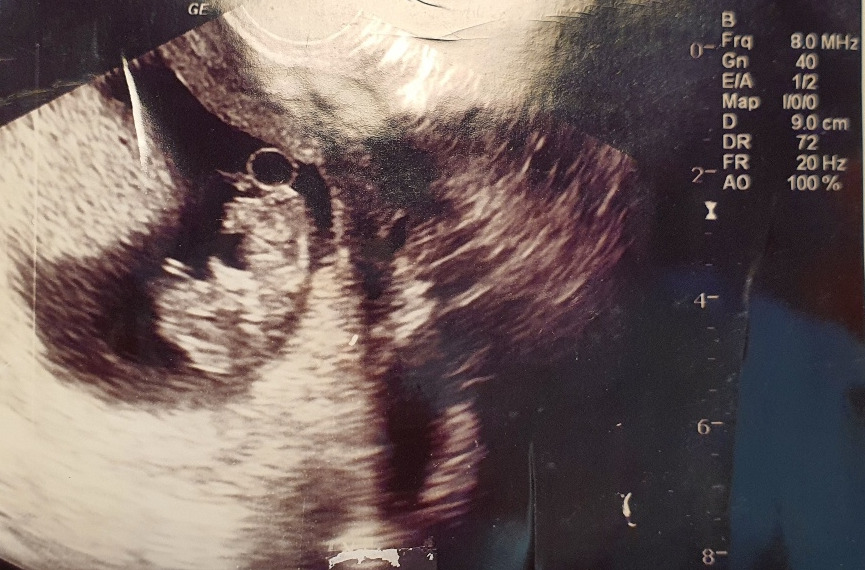

아기의 심장소리를 처음으로 듣던 날이 아직도 생생하게 기억난다. "뜨꾸 뜨꾸 뜨꾸" 아기는 살아 있음을 소리로 힘차게 말하고 있었다. 아기의 심장소리를 듣자 내가 엄마가 됐다는 일이 실감이 났다.

10주 차 병원 진료 일이 되었다.

아이는 얼마나 컸을까? 심장 소리도 다시 들을 수 있겠지? 설렘의 발걸음으로 진료실 문을 활짝 열었다.

초음파로 아이를 보던 의사 선생님의 표정이 좋지 않다. 뭔가 잘못된 걸까? 의사와 간호사 모두 말을 아낀다.

그제야 정신을 차리고 의사 선생님을 쳐다보았고, 의사 선생님은 갈 길을 잃은 나의 눈을 바라보며 아기의 심장소리가 들리지 않는다고 말했다.

계류유산... 태어나 처음으로 들어본 말이었다.

계류유산이란? 임신이 되고 초음파에서 아기집도 보이나 발달과정에서 태아가 보이지 않는 경우 또는 임신초기에 사망한 태아가 유산을 일으키지 않고 자궁 내에 잔류하는 경우를 말한다고 한다.

나의 경우에는 두 번째에 해당되는 임신초기 태아가 사망한 채 자궁 내에 잔류하는 경우였다.